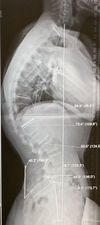

Imaging

CXR: ARDS, exclude perforated DU

Contrast CT: Balthazar severity score

What is used to grade severity of pancreatitis on CT?

Balthazar severity score